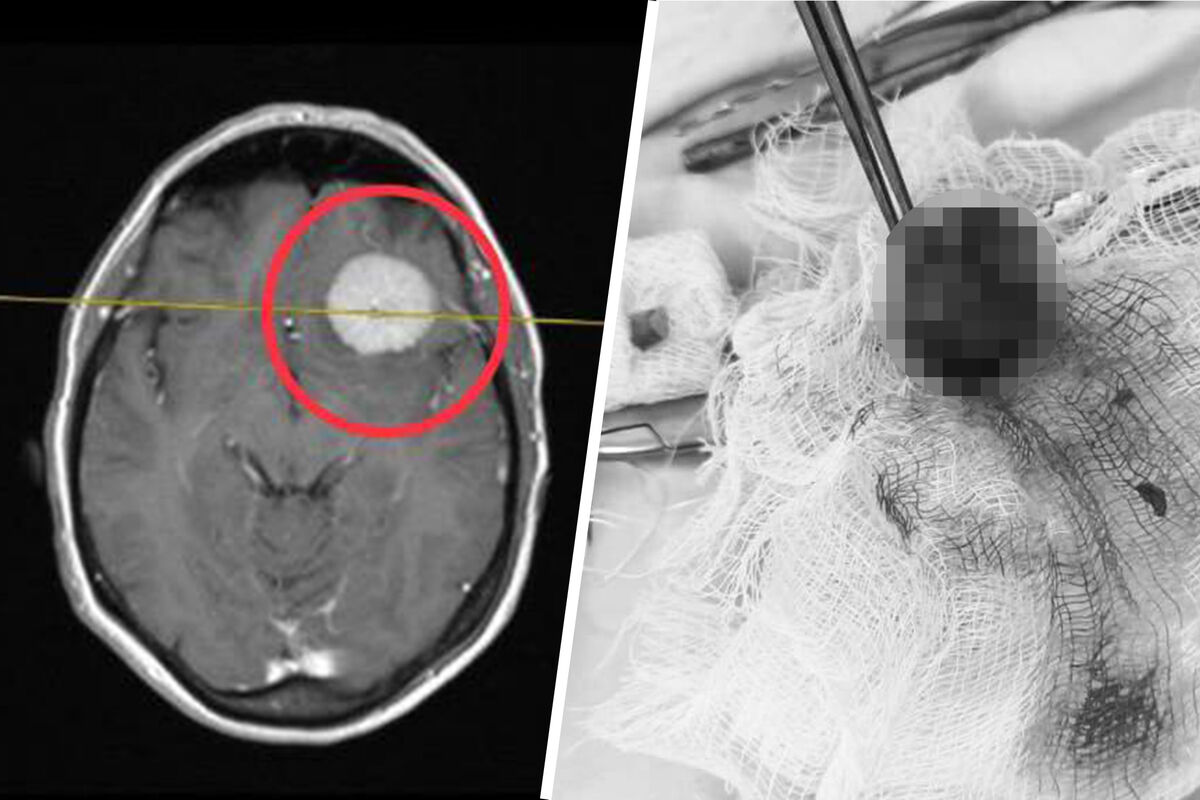

Опухоль мозга размером с куриное яйцо удалили пациентке подмосковные хирурги

В Подмосковье хирурги удалили пациентке опухоль мозга размером с яйцо

Нейрохирурги Коломенской больницы спасли женщину с огромной опухолью головного мозга, новообразование полностью удалили. Об этом сообщает минздрав Московской области.

54-летняя жительница Коломны была госпитализирована с острой головной болью. В ходе обследования в головном мозге пациентки была обнаружена опухоль размером с куриное яйцо. Было принято решение о проведении хирургического вмешательства.

«Операция продолжалась около 4 часов. Выполнив трепанацию черепа, нейрохирурги с помощью операционного микроскопа и нейрохирургических инструментов удалили объемное образование основания черепа», — сообщили в больнице.

Опухоль оказалась доброкачественной, некоторое время пациентка находилась под наблюдением врачей и была выписана на амбулаторное лечение. Для исключения рецидива ей необходимо будет регулярно наблюдаться у врача-невролога по месту жительства.